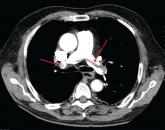

NewsHow to manage submassive pulmonary embolismAuthor:Haiyun Wang, MDPublish date: August 14, 2017Use pulmonary angiographic data, clinical stability, and analysis of other comorbid conditions to decide the best treatment modality for an individ...Read More